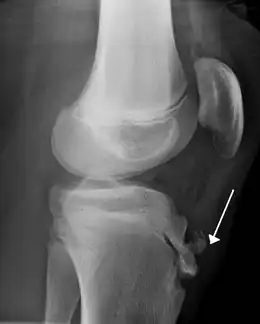

IRM d'un Osgood-Schlatter- Radiographie d'un Osgood-Schlatter

Une radiographie n'est pas nécessaire notamment lorsque le tableau clinique est évocateur et que les douleurs sont bilatérales. Elle peut être utile pour éliminer une autre pathologie si les douleurs sont unilatérales, atypiques ou rebelles au traitement. Initialement on retrouve un soulèvement de la tubérosité tibiale antérieure avec élargissement de son cartilage de croissance ; dans les stades plus évolués, la TTA est fragmentée et on peut voir parfois des calcifications dans le ligament rotulien[2].